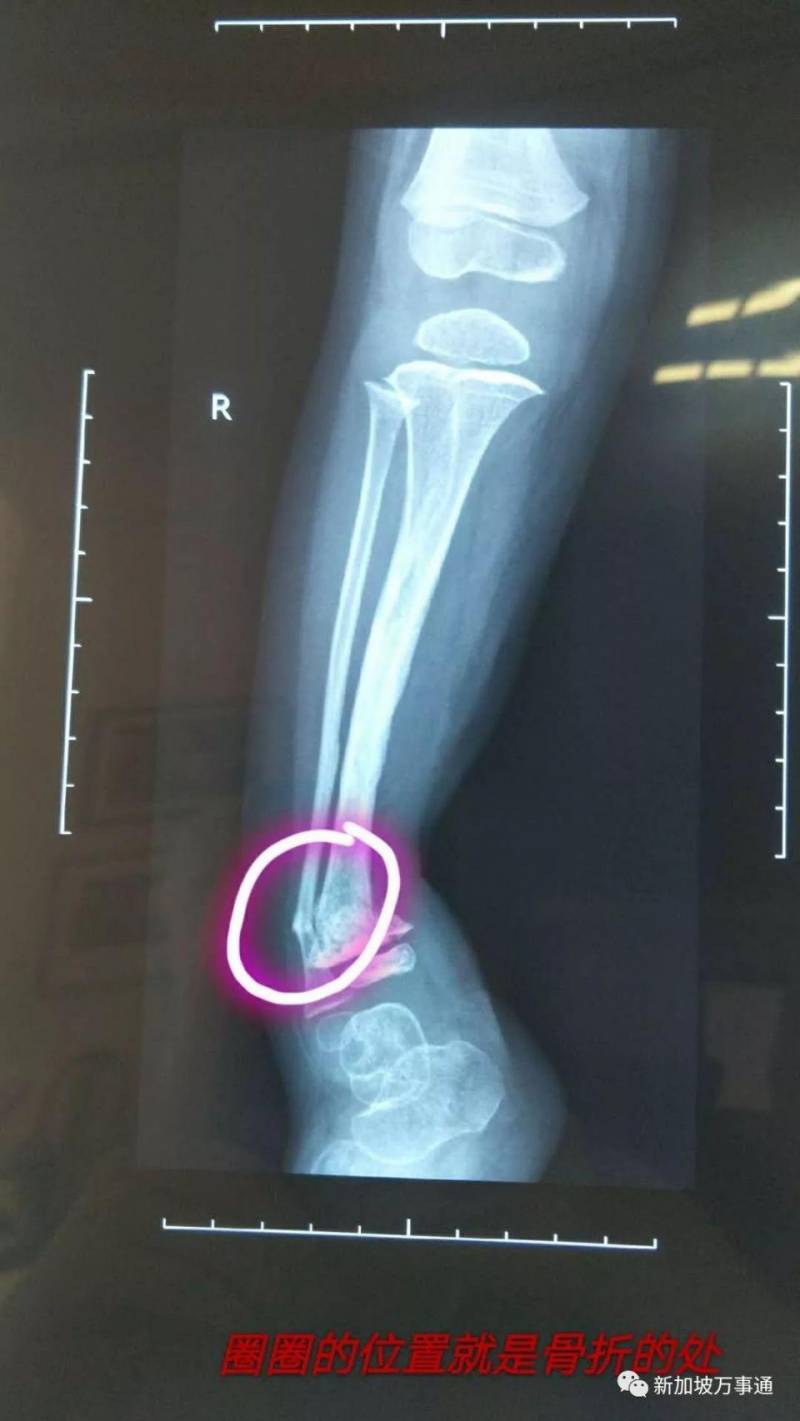

可在最后一疗上疗前,莎莎的右小腿肿瘤切除处腿骨骨折。

医生评估:说要等化疗全部做完结束,血项正常了才能安排手术,手术费用要2万新币。5月3号已上完最后一次疗程化疗,莎莎的血项恢复正常就马上手术。